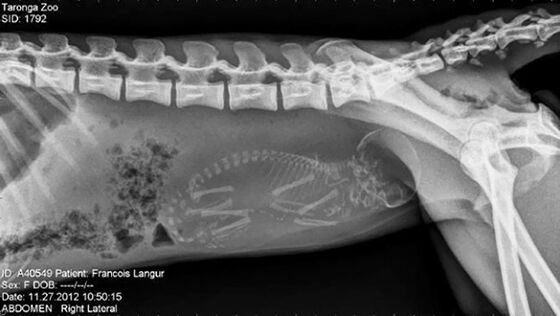

3. Monyet Francois Langur